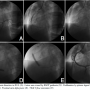

His electrocardiogram revealed ST elevation in leads II, III, and avf. He was treated with intravenous nitrates, aspirin, clopidogrel, beta-blocker, and atorvastatin. After receiving eptifibatide, he was transferred for coronary angiography and subsequent intervention. Cardiac catheterization revealed a long dissection in the right coronary artery (RCA) from mid segment to the distal part with thrombus. The other coronary arteries were normal. The left ventricle had akinesia in the infero-posterior segments. The ejection fraction was 35%. RCA ostium was engaged with right Judkins 3.5 7 Fr guide catheter. The area of dissection was crossed with a BMW guidewire with difficulty. Aspiration catheter did not cross. A 2 mm x 10 mm balloon (Sprinter Legend, Medtronic) was placed into the distal portion of the RCA and inflated sequentially to prepare the bed. Two endeavor resolute stents (3.5 mm x 24 mm, 4.0 mm x 30 mm) were deployed at 16 atm across the lesion. Both the stents were post-dilated. TIMI III flow restored with resolution of the ST segment elevations, and abolishment of chest pain. Intracoronary adenosine and nicorandil were given beforehand.